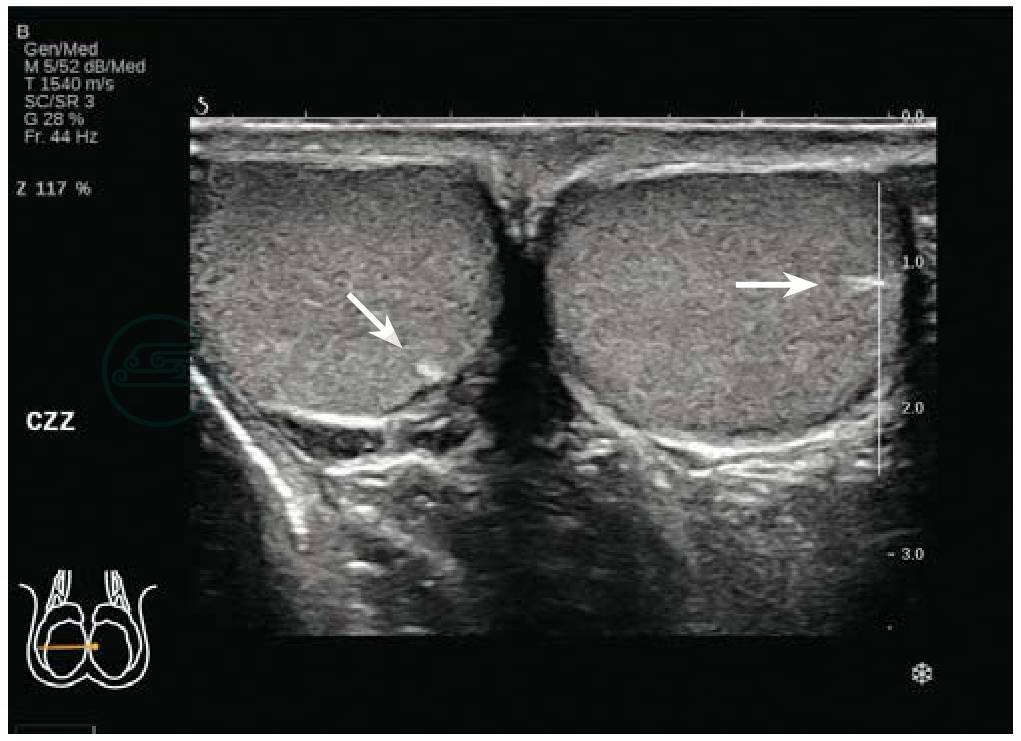

位于两侧阴囊内,左右各一(图6-1)。

图6-1 正常睾丸

睾丸横切,箭:睾丸纵隔